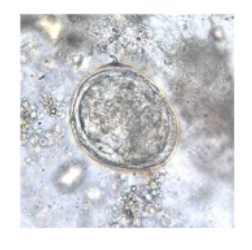

What parasite does this egg belong to?

Ascharis lumbricoides (nematoda)

Trichuris Trichuria (nematoda)

Schisstosoma (platyhelminthes)

Taenia species

Name what parasite this egg belongs to?

Ascaris lumbricoids (fertilised egg)